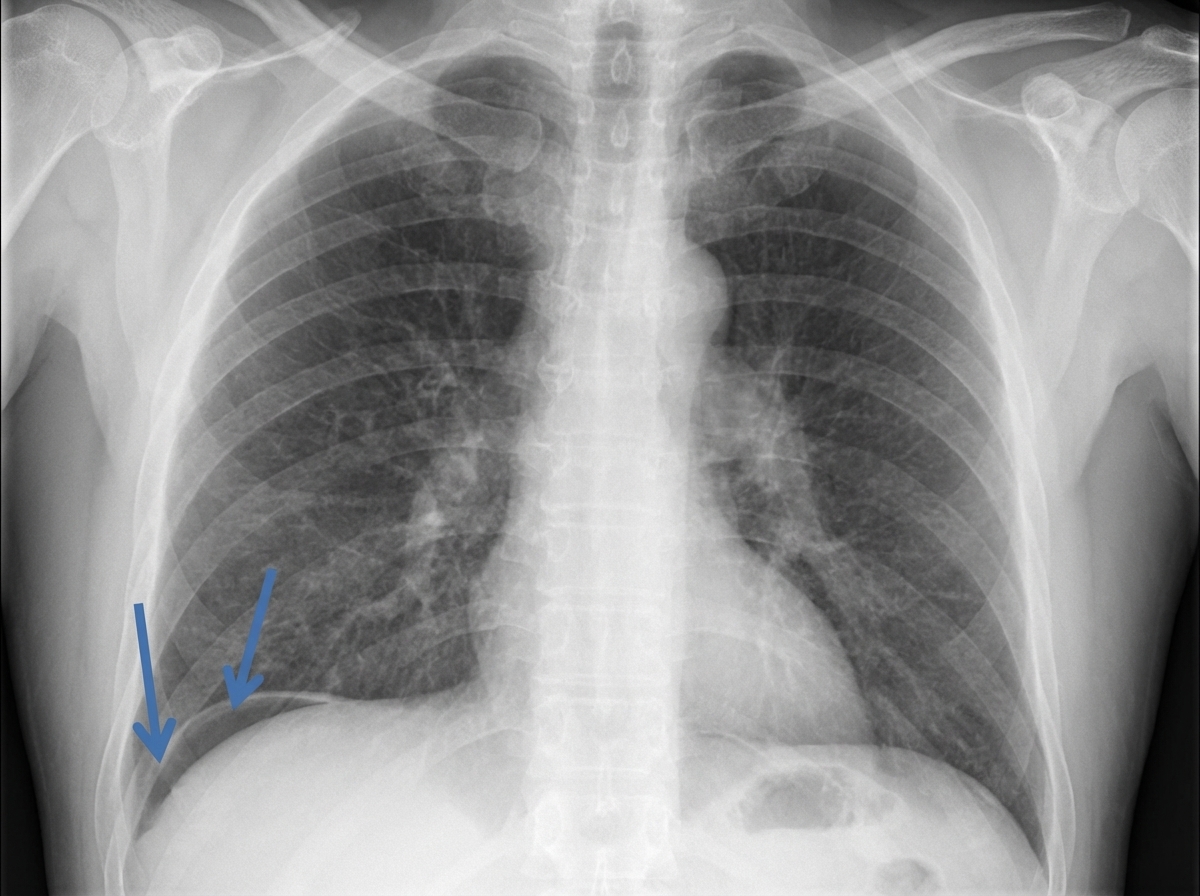

Question 61: In the image shown below, which of the marked area is involved in relieving pain in response to massage?

- A. Area A (Correct Answer)

- B. Area B

- C. Area C

- D. Area D

Explanation: ***A*** - Area A points to the **dorsal columns** (specifically the fasciculus gracilis and cuneatus) of the spinal cord, which carry **mechanoreceptive** and proprioceptive information. - Massage activates large diameter afferent fibers which transmit signals via the dorsal columns, inhibiting pain transmission through the **gate control theory of pain**. *B* - Area B points to the **dorsal horn** (specifically lamina I, II, and V), which is primarily involved in receiving and processing **nociceptive input**. - While integration of pain occurs here, it is not the primary pathway for the **modulatory effects of touch/pressure** from massage for pain relief. *C* - Area C indicates the **ventral horn** of the spinal cord, which contains **motor neurons** that control skeletal muscle activity. - It is involved in motor output, not directly in the sensory processing or modulation of pain signals from massage. *D* - Area D points to the **lateral white matter**, which contains various ascending and descending tracts, including the **spinothalamic tract** (primary pain pathway) and corticospinal tract. - While the spinothalamic tract carries pain signals, the direct pain-relieving effect of massage primarily involves activation of mechanoreceptors whose signals ascend via the dorsal columns.